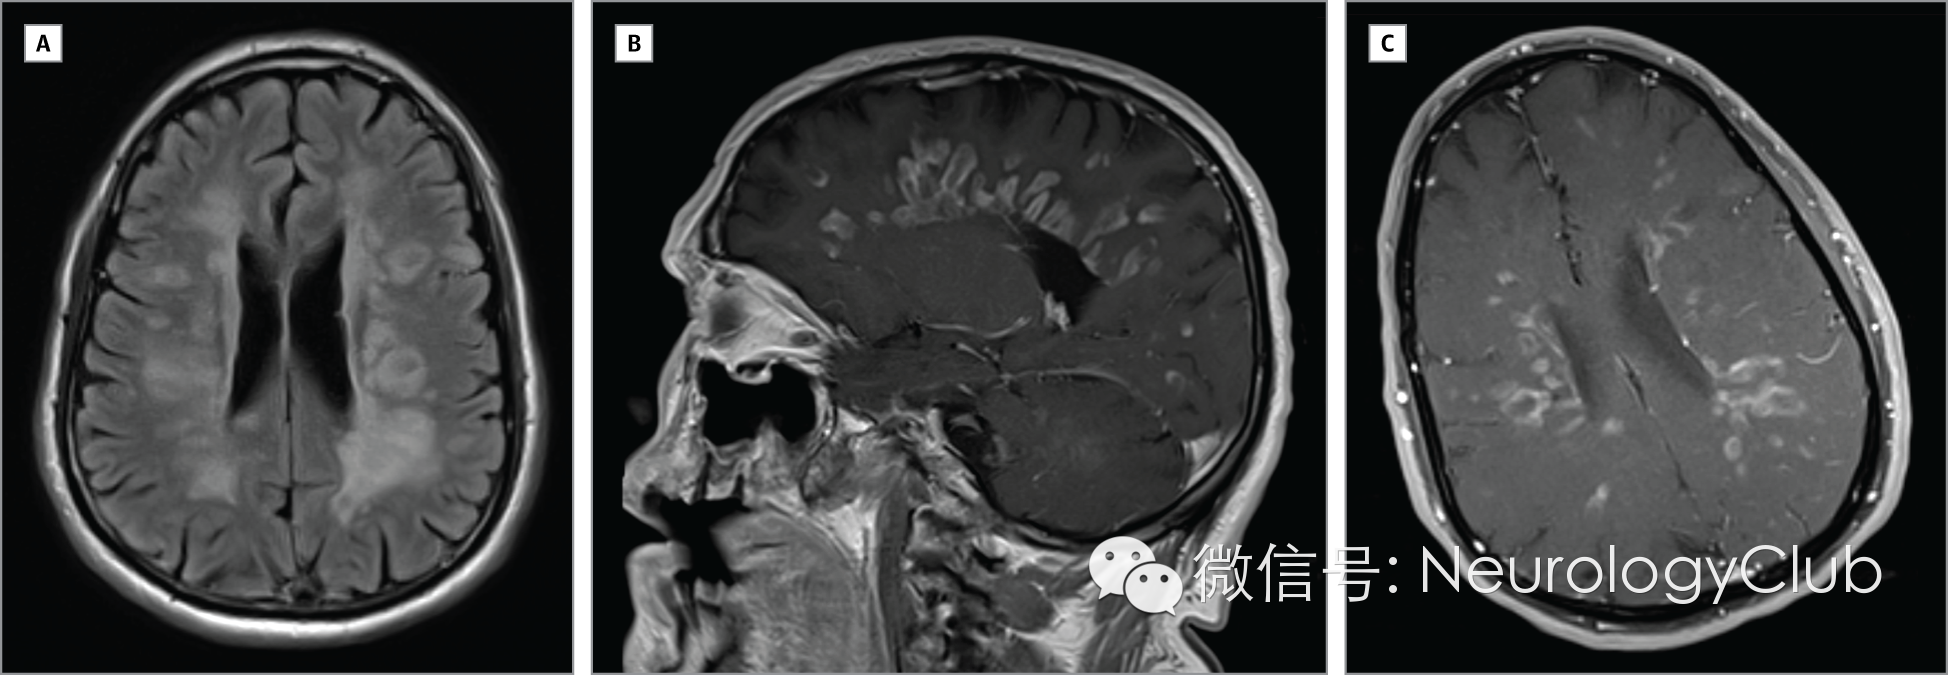

脑脊液检查白细胞50个,全为淋巴细胞。寡克隆带很少。病毒(包括HIV)和细菌学检测阴性。头颅MRI提示颅内多发T2高信号,环形强化病灶,不伴有弥散受限。

(图 A:FLAIR;B-C:增强)